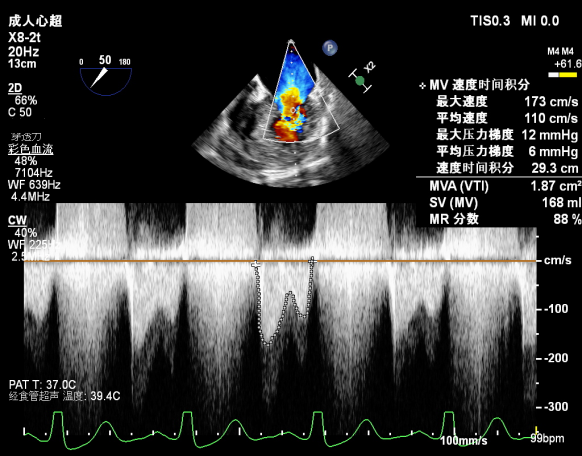

Bicom:MR(重度),反流束宽9.6mm,反流面积15.7cm²

PISA法定量EROA:1.05cm²,Rvol:148ml,RF:58%。

肺静脉血流频谱呈收缩期反向

二尖瓣口平均跨瓣压差:6mmHg